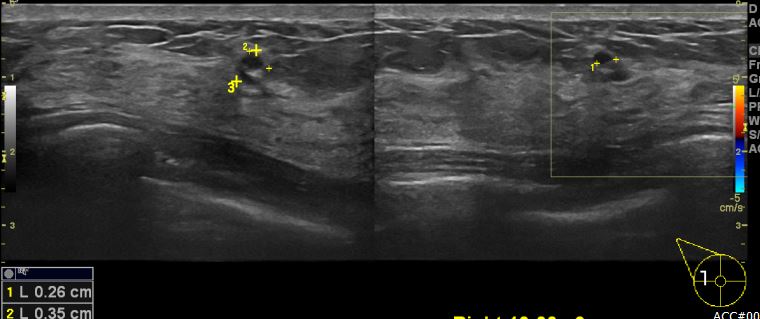

양측 유방에 만져지는 멍울로 내원하신 40대 여성분으로 유방 초음파 시행 후 우측 9시

방향에 의심스러운 혹 조직검사 시행하여 우측 유관암 진단 되었습니다.